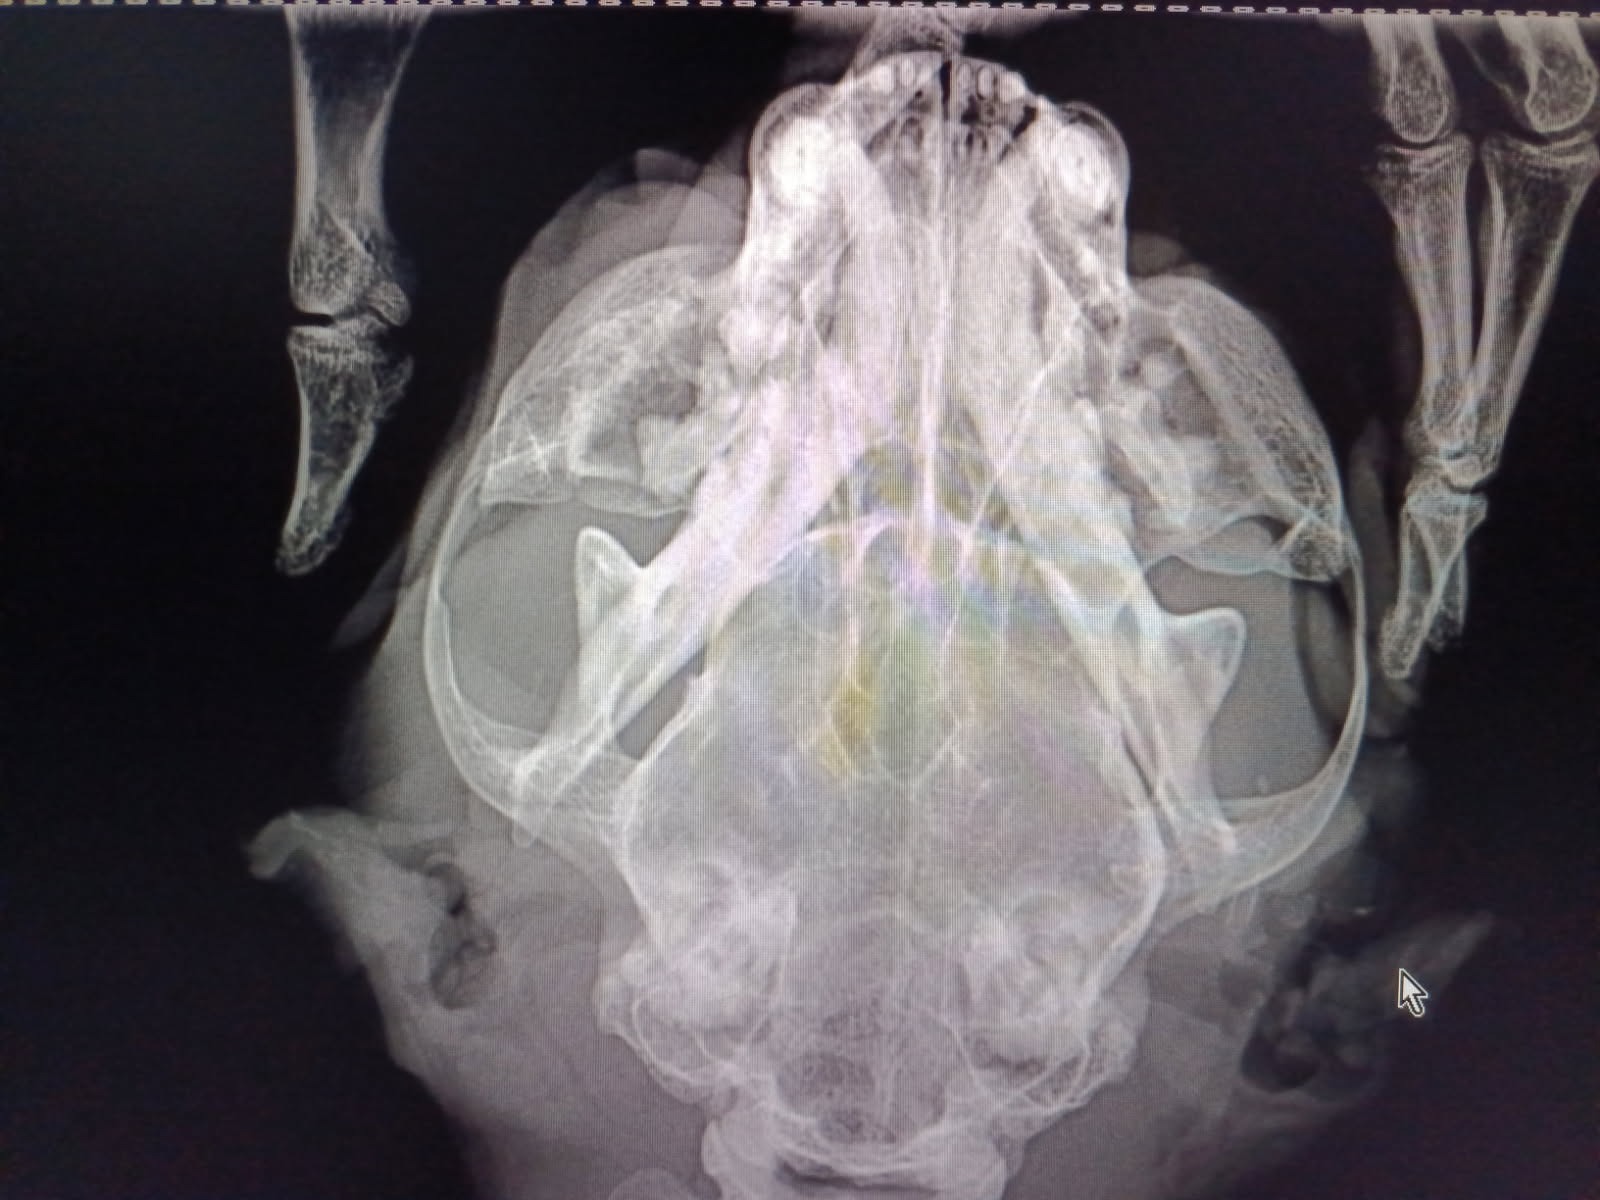

Para já, o Oreo não pode regressar à rua: sofreu um traumatismo que lhe fracturou ambos os maxilares. No raio X pode ter-se, do lado esquerdo, uma factura do ramo da mandíbula.

Felizmente, não tem outras fracturas nem hemorragias internas, o que possibilitou um prognóstico optimista. Na manhã seguinte à captura, o Oreo já mostrava apetite.